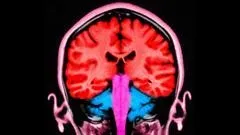

Recent research indicates that electrical stimulation targeting specific brain areas can influence levels of selfishness in individuals. When applied to the frontal and parietal lobes, this stimulation appears to increase participants’ willingness to share financial resources, reflecting a temporary shift towards more altruistic behavior. These findings not only illustrate the potential of brain stimulation in modifying behavior but also raise questions about the ethical implications of altering our natural inclinations towards selfishness. As we delve deeper into how brain stimulation reshapes behavior, it becomes clear that our understanding of free will and moral responsibility is intertwined with neuroscience.

Yes, electrical stimulation has been shown to reduce selfish behavior temporarily by targeting specific areas of the brain involved in decision-making and empathy. A study from the University of Zurich demonstrated that when both frontal and parietal areas of the brain were stimulated, participants were more willing to share resources, indicating a potential for electrical stimulation to influence altruistic behavior.

The study found that stimulating two areas of the brain led to an increase in donations among participants. This suggests that electrical stimulation can temporarily enhance selflessness by improving how individuals weigh their own interests against those of others, thus highlighting the neuroscience of altruism.

Electrical brain stimulation can activate neural circuits associated with empathy and altruism, leading to more selfless decisions. Researchers discovered that changing the communication within these brain networks through stimulation can alter how people prioritize their interests against the interests of others.

| Methodology | 44 volunteers participated, deciding how to split money with a partner under brain stimulation. |

| Brain Areas Stimulated | Profrontal and parietal lobes, involved in decision-making and empathy. |

| Key Findings | Participants who received stimulation donated more money than those who did not. |